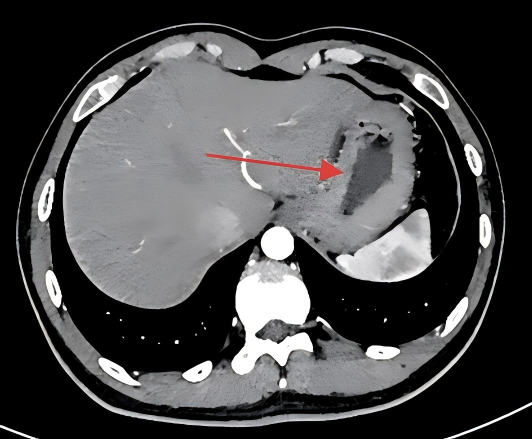

左起:图1a图1b

图1b检查时患者充分饮水,胃腔被撑开(红色箭头),胃壁变薄。此时若存在异常增厚的胃壁(比如炎症或肿瘤),就不会容易漏掉疾病,能更清楚的发现疾病。